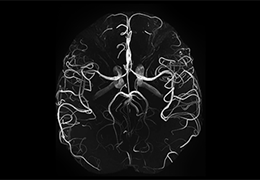

ART-Plan™ Artificial Intelligence Contouring